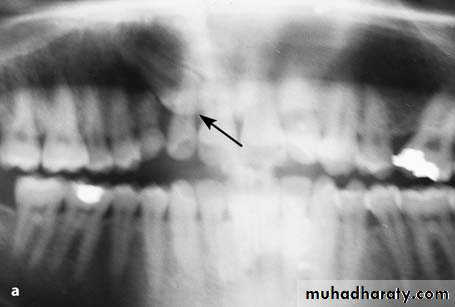

Radiographic features

classified into eumorphic (similar to a normal-sized central incisor) and dysmorphic

three common dysmorphic shapes

• conical or peg shaped (most common ~70%)

• tuberculate (more than one cusp or tubercle)

• supplemental (duplication of a normal tooth)

55% grow in the downward position (35% are inverted and 7% are horizontal)

most remain impacted but 25% will erupt (usually eumorphic or conical shape)